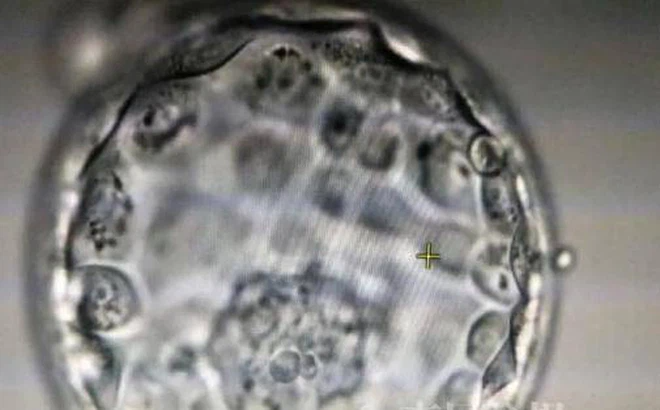

Xét thấy phôi trữ đông lâu và chị Tân thuộc nhóm thai phụ nâng cao nên phôi thai sống thành công tiếp tục được nuôi cấy thành phôi nang trong ống nghiệm rồi cấy vào phôi thai. Vào tháng 5 năm 2020, cô Tân trải qua ca phẫu thuật cấy ghép đầu tiên và không thành công . May mắn thay, sau ca phẫu thuật cấy ghép thứ hai, phôi thai đã được cấy thành công và chị Tân đã mang thai.